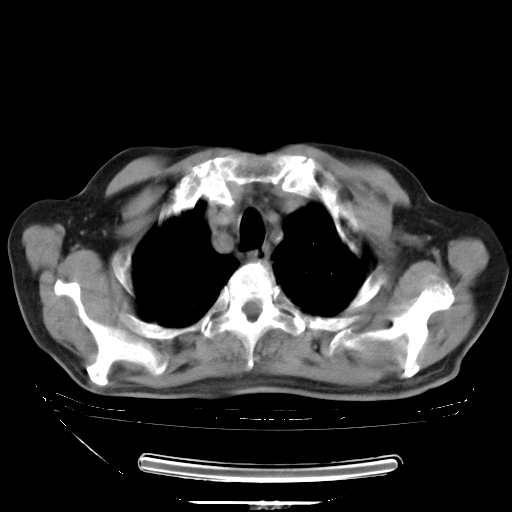

今天复查肺部CT,发现双肺广泛磨玻璃样改变。所以我把3月19日和5月9日相隔50天的肺部CT上传。请大家会诊。

2009年3月19日肺部CT片。

2009年3月19日肺部CT

大致读了系列胸部CT:纵隔窗无明显异常,肺窗:从4、27至今:主要是双肺中下野外带可见毛玻璃样改变,目前处于急性肺泡炎阶段,至于原因考虑1、结替组织或胶原血管性疾病所致?2、恶性疾病如恶组在肺部所致的表现或细支气管肺泡癌?3、药物或其它原因如肺蛋白沉着症所致肺泡炎目前不太可能?总之,明天就去请我院的呼吸科、感染科、血液科和临免专家会诊哈。